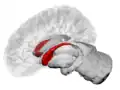

The caudate nuclei are near the center of the brain, sitting astride the thalamus. There is a caudate nucleus in each hemisphere of the brain. Each nucleus is C-shaped, with a wider "head" (caput in Latin) at the front, tapering to a "body" (corpus) and a "tail" (cauda). Sometimes a part of the caudate nucleus is called the "knee" (genu).[7] The caudate head receives its blood supply from the lenticulostriate artery; the tail of the caudate receives its blood supply from the anterior choroidal artery.[8]

The head and body of the caudate nucleus form part of the floor of the anterior horn of the lateral ventricle. The body travels briefly towards the back of the head; the tail then curves back toward the anterior, forming the roof of the inferior horn of the lateral ventricle. This means that a coronal section (on a plane parallel to the face) that cuts through the tail will also cross the body and head of the caudate nucleus.

Caudate nucleus highlighted in green on sagittal T1 MRI images